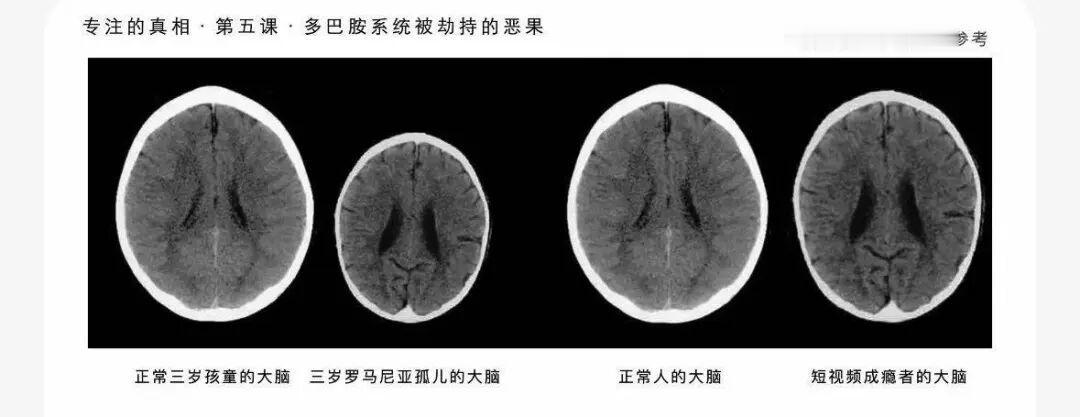

你的大脑正在被“重塑”?10万人数据揭开短视频的残酷真相 本想刷十分钟放松,抬头一看两小时过去了;刷时哈哈一笑,放下手机却感到一阵空虚和焦虑。如果你有同感,记住,这不是你意志力薄弱,而是你的大脑正在被“重塑”。 今年,一项发表在心理学顶刊、覆盖全球近10万人的研究给出了扎心结论:短视频刷得越多,认知能力和心理健康状况往往越差。 为什么我们像着了魔一样停不下来?研究揭示,这就像一场大脑的“劫持”。 我们的大脑原本是为狩猎和采集设计的,现在却被强行训练每15秒接收一次高强度刺激。后果就是“习惯化”——吃惯了麻辣火锅,谁还尝得出白米饭的香味?脑电图显示,重度用户的P300脑波(负责注意力)显著降低,大脑真的变“迟钝”了。 更可怕的是“瘾”的形成机制。下一个视频是惊喜还是无聊?这种“不可预测性”就像赌博,疯狂刺激多巴胺分泌。 长期下来,大脑结构甚至改变:管自控的前额叶皮层“萎缩”,管欲望的纹状体异常活跃。等于理性的“司机”睡着了,欲望的“油门”却被焊死。 最讽刺的是,我们本想靠刷视频解压,结果却适得其反。看着别人滤镜下的完美生活,潜意识里在进行残酷的“社会比较”,压力不减反增。 别以为只有孩子才会上瘾,成年人的大脑同样脆弱。 如果你符合以下几条,警报已经拉响: • 计划刷10分钟,结果失控刷了2小时。 • 手机不在身边就心慌意乱。 • 为了刷视频推迟正事,影响生活。 • 明知有害,却停不下来。 好消息是,大脑具有可塑性,我们可以把它“修好”。 无需彻底戒断,关键在于从“被控制”变为“掌控者”: 1. 物理隔离: 睡前把手机请出卧室,这是最有效的一招。 2. 增加步骤: 把App藏到文件夹深处,每次打开多点几下,给理智争取时间。 3. 黑白模式: 让手机屏幕变成黑白,吸引力瞬间减半。 4. 内容大清洗: 取关让你焦虑的账号,让算法成为你的学习工具,而非娱乐奴隶。 家长们尤其注意,没收手机是最差策略。如果你瘫着刷手机,孩子不会听你的说教。 带他去户外、去运动,用真实世界的精彩填满生活。 你的注意力,是这个时代最宝贵的资产。别让它,被廉价地收割了。 从今天起,每天改变一点点,重掌你生活的方向盘。